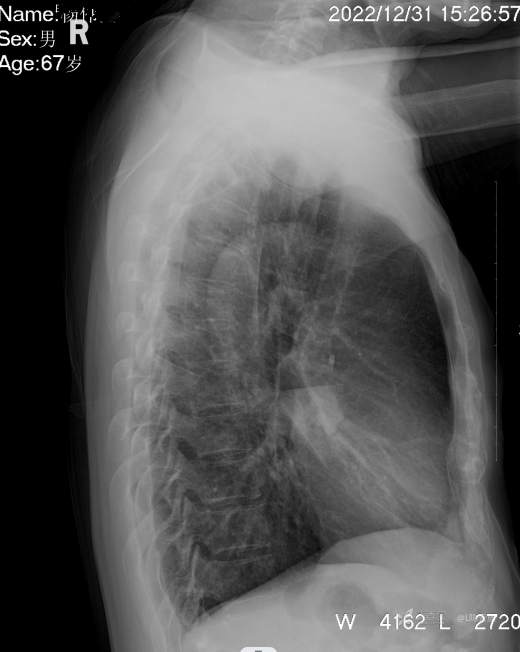

1、男67岁,精神病长期住院患者,发烧,伴咳嗽气紧两天。

2、又是胸片典型病例,你能正确描述和准确诊断吗?